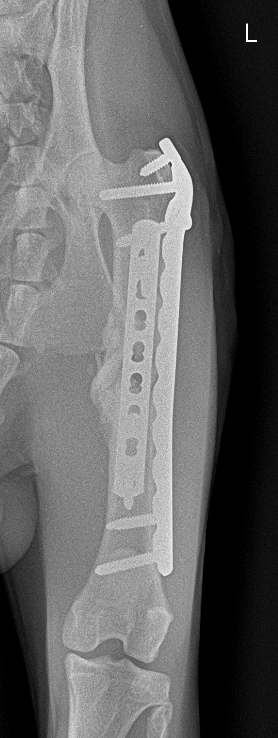

画像だと少しわかりにくいかもしれませんが、骨が癒着しぶらぶらだった状態からしっかりと固まってきております。

術後1ヶ月